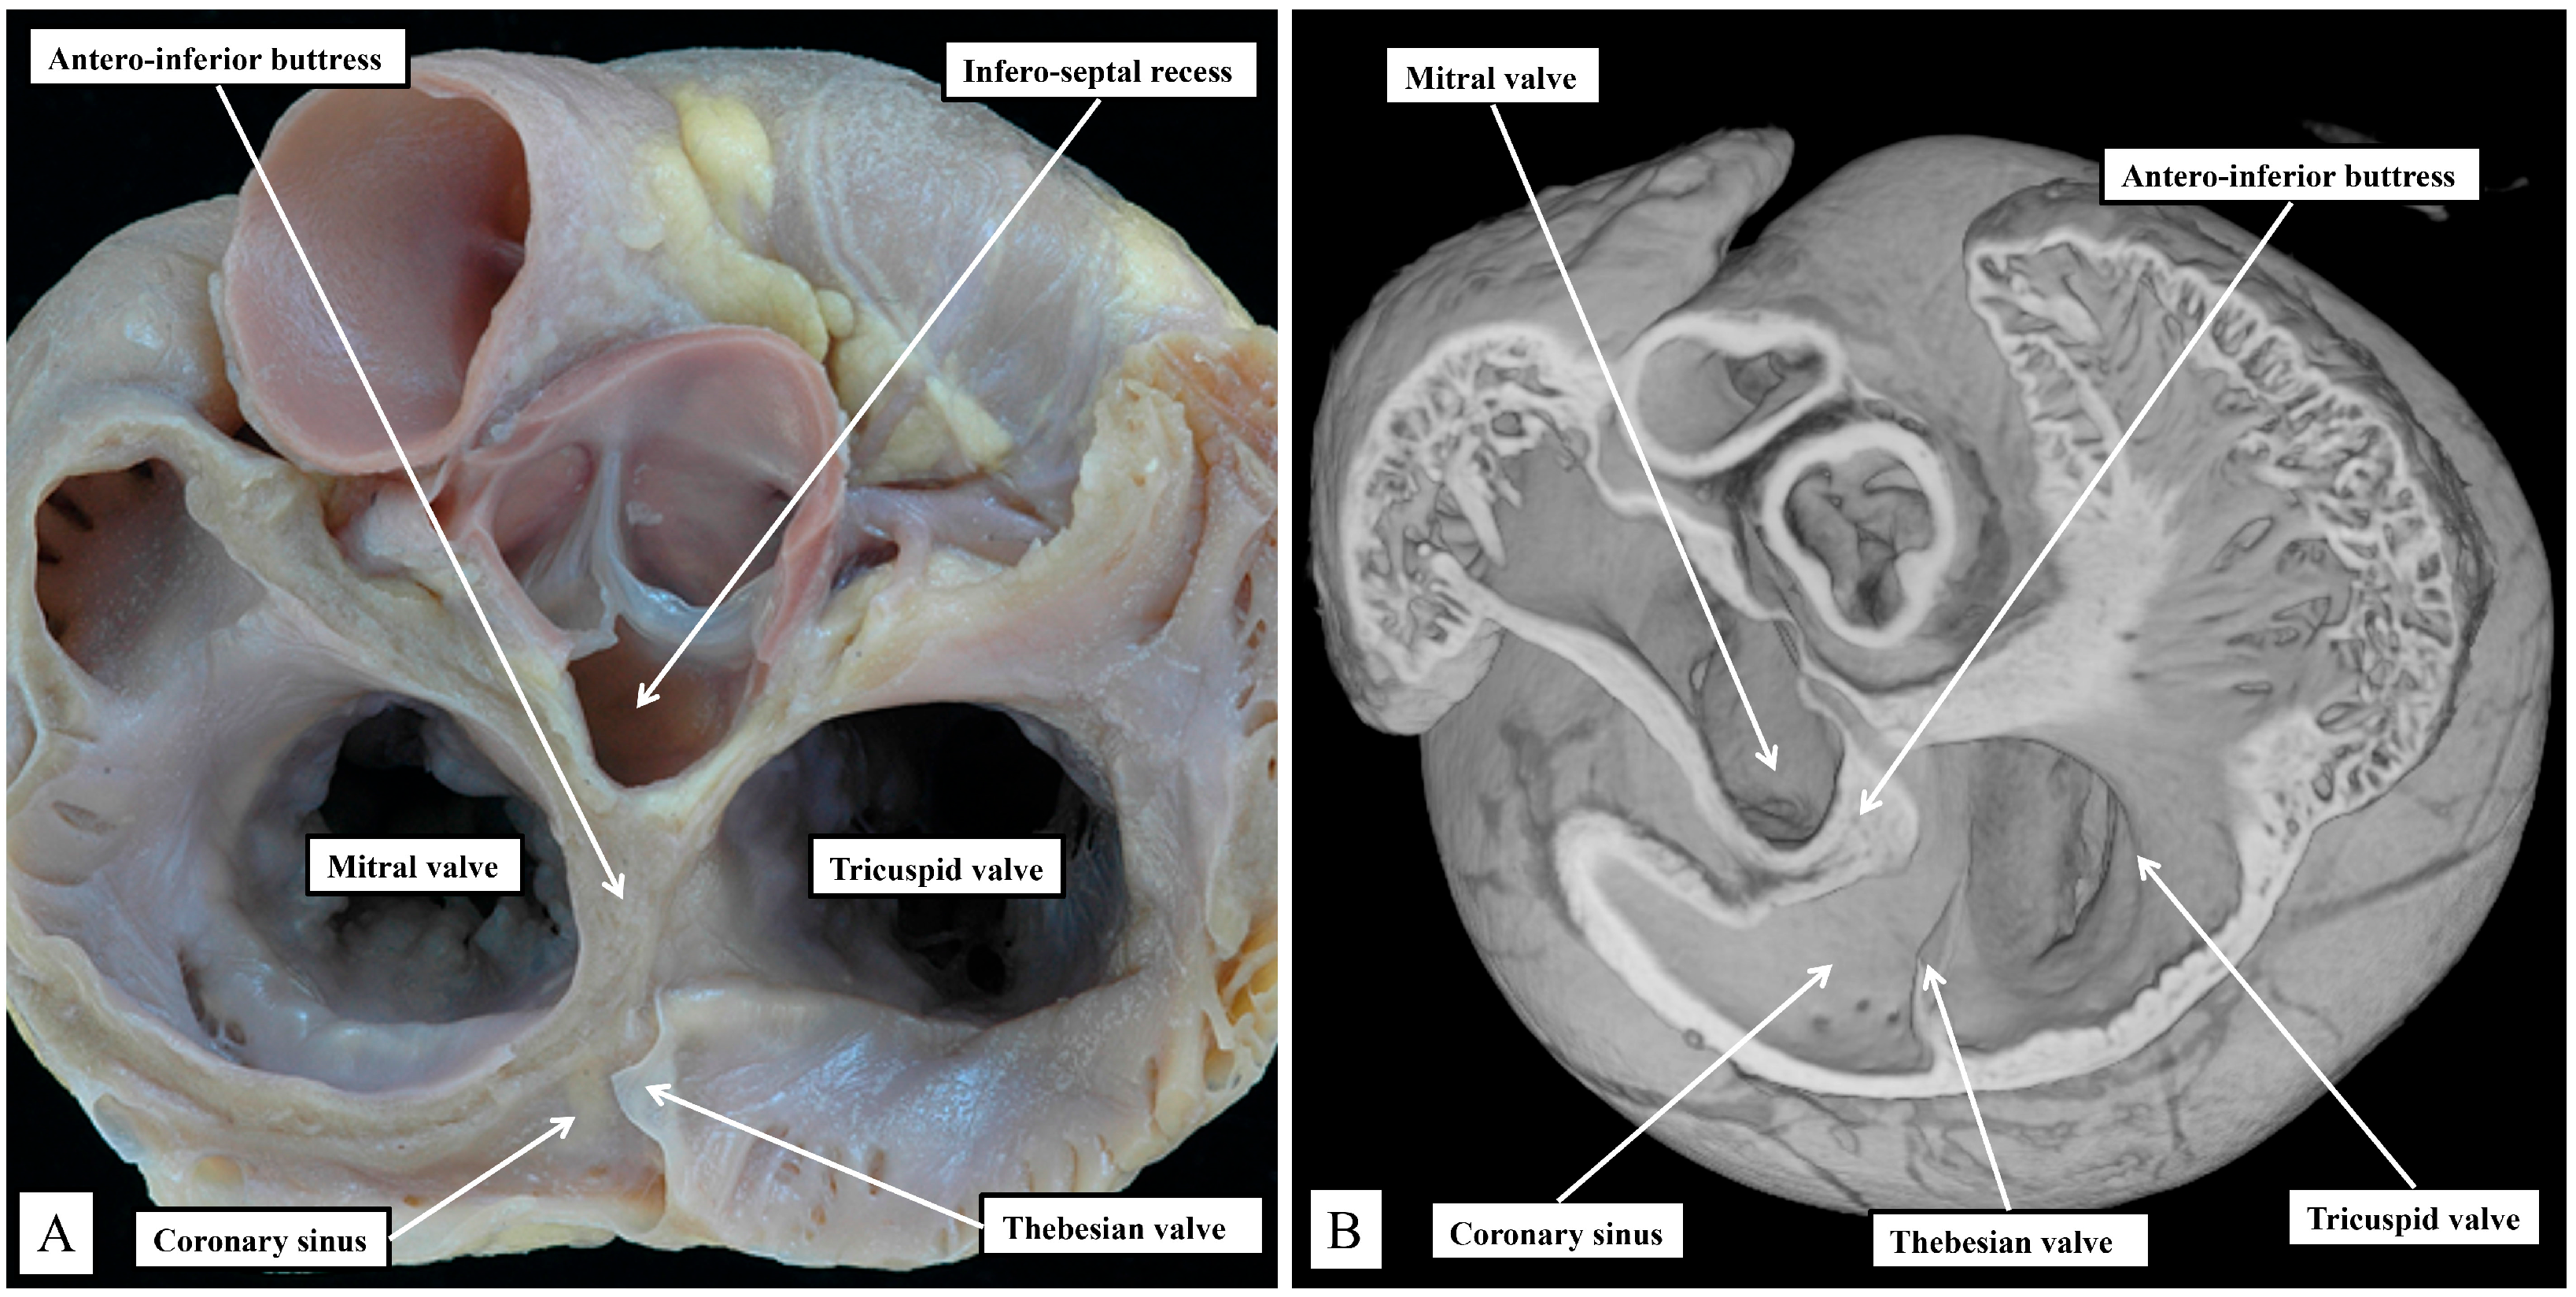

In the human heart, the coronary sinus serves only as the conduit for the return of the greater part of the venous drainage of the heart since the left superior caval vein has usually regressed in the human heart, with its walls persisting only as the ligament of Marshall. In the murine heart, as already explained, it is the norm for the left superior caval vein to persist, and to open to the right atrium through the orifice of the coronary sinus. This produces a marked difference in the relationship of the orifices of the right and left atrioventricular junctions, guarded by the tricuspid and mitral valves (Figure 3).

In the murine heart, furthermore, as previously noted by Icardo and colleagues [16], it is often difficult to find a third leaflet guarding the right atrioventricular junction (Figure 3B), whereas, in the human heart, the right atrioventricular valve usually closes in trifoliate fashion, even though it may be difficult to find a zone of apposition supported by discrete papillary muscles between the inferior and the antero-superior leaflets. The other major difference to be noted in the junctional arrangements, however, is the much deeper “wedging” of the aortic root between the leaflets of the mitral valve and the septum (Figure 3A). The combination of the enlarged orifice of the membranous septum and the lack of aortic wedging in the murine heart means that, although there is an infero-septal recess between the aortic leaflet of the mitral valve and the septum, it does not extend beneath the antero-inferior buttress of the atrial septum to the same extent as is seen in the human heart [17]. The inferior pyramidal space, furthermore, does not extend as far superiorly in the murine heart as in the human heart. This, again, reflects the differing relationships between the orifices of the right and left atrioventricular junctions (Figure 3), and the presence in the murine heart of the persistent left superior caval vein (Figure 3B). In the human heart, the inferior pyramidal space extends beneath the antero-inferior buttress of the atrial septum, being confined by the diverging walls of the right and left atrial vestibules [17]. In the murine heart, the vestibule of the right atrioventricular junction itself extends much more inferiorly, having to receive the enlarged orifice of the coronary sinus (Figure 3B). In the human heart, it is the extensive superior extent of the inferior pyramidal space that serves to place the septal wall of the right atrial vestibule adjacent to the inferior extent of the infero-septal recess of the left ventricular outflow tract [17]. These relationships, as we will explain, then determine the equally subtle differences in the location of the atrioventricular conduction axis relative to the septal landmarks in the human heart as opposed to the murine heart. The differences can be demonstrated by making a cut that removes the right atrial walls of the human heart, leaving behind the rims and floor of the oval fossa, but extending through the antero-inferior buttress of the atrial septum so as to cut into the infero-septal recess (Figure 4A). The part of the heart thus revealed, having removed the ventricular septal components to show the parietal components of the left ventricle, then shows how the apex of the inferior pyramidal space, extending superiorly, meets the inferiorly directed apex of the infero-septal recess (Figure 4B).

Figure 3. Panel (A) Human heart, Panel (B) Murine heart. The images are prepared by removing the atrial walls and the arterial trunks and photographing the atrioventricular junctions from the atrial aspect. The marked differences are discussed in the text.